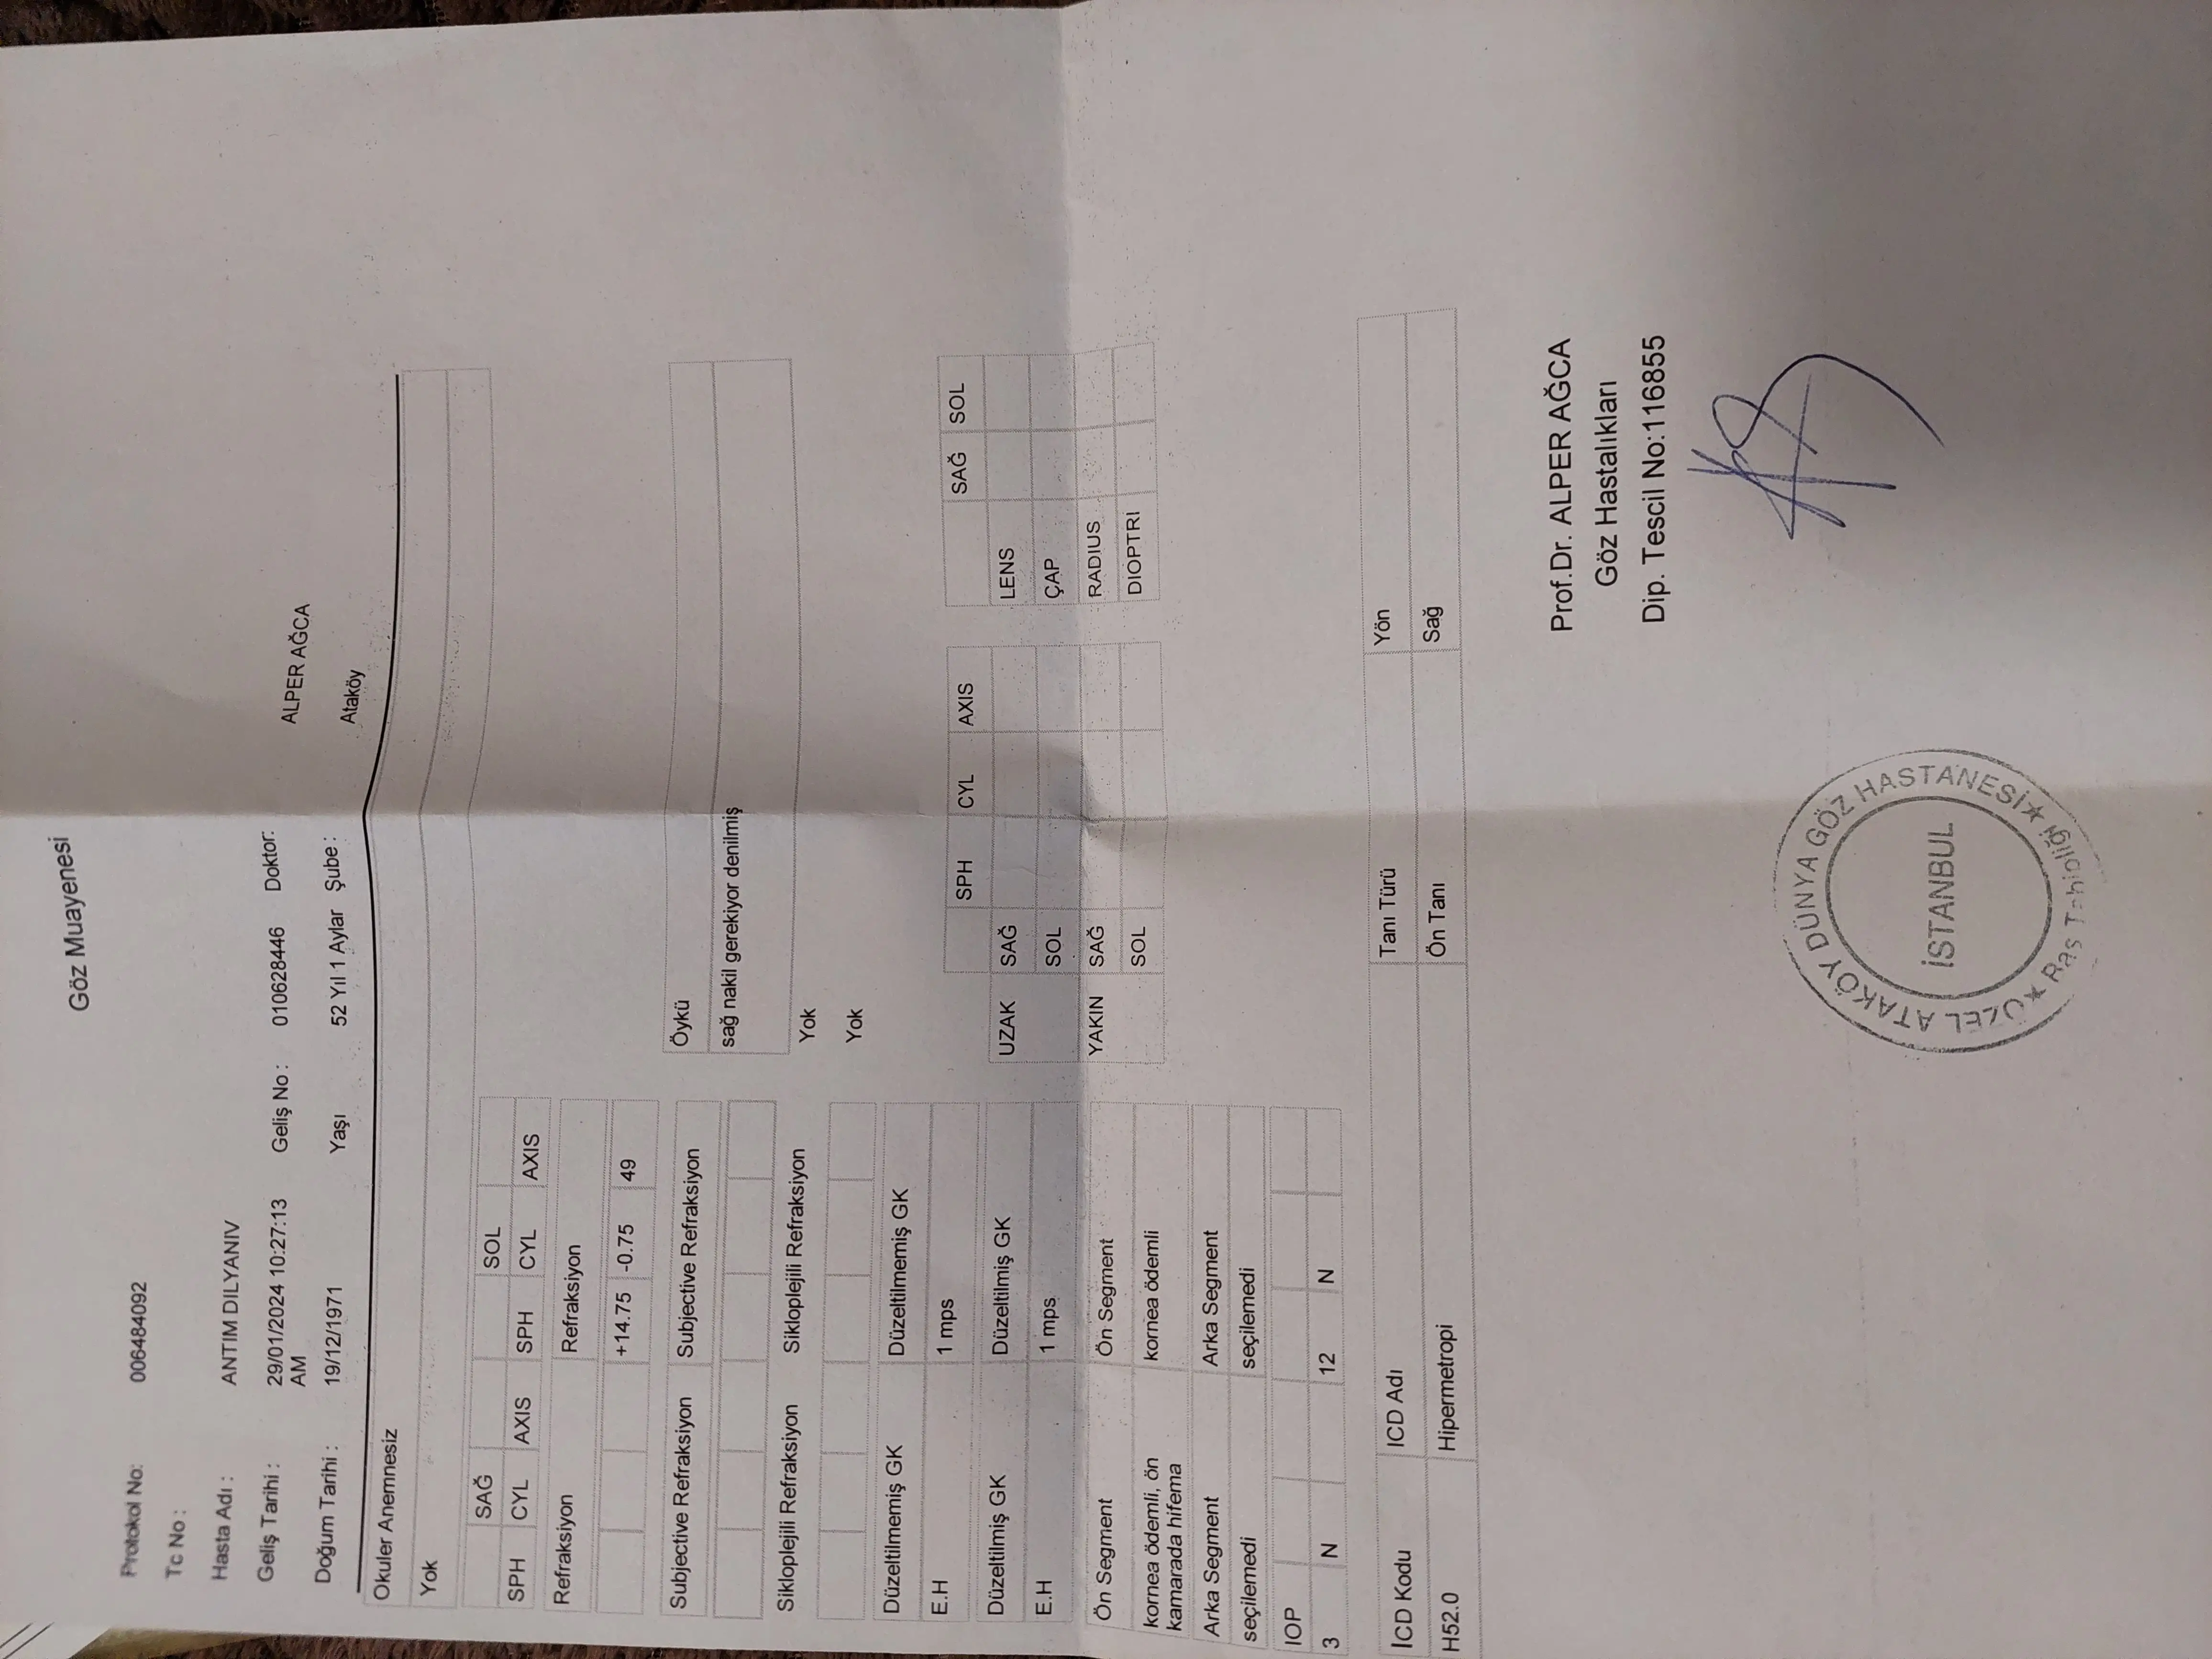

Преглед в Турция на 29.01.2024 г. Review in Turkey on 29.01.2024

Мили хора, посетихме професор Алпер Агча, специалист по роговична трансплантация. Той потвърди диагнозата за силно изтъняване и помътняване, която изисква смяна, тъй-като цветната снимка е в лилаво, което показва необходимостта от трансплантация. Но се появи и друг проблем - кръвоизлив, като при това се превръща във фиброзна тъкан, захващаща се в ретината и има опасност от отлепване.

Професор Музалер, специалист по болести на ретината, препоръча спешна витректомия и трансплантация в една сесия до един месец най-късно.

Моля ви от сърце да ни помогнете. Предоставям двете оферти за операциите, докато ни издадат една обща и снимки от прегледите при двамата професори. В сметката на болницата са останали 1200 евро, които ще се прибавят към сумата за операциите.

Dear folks, we visited Professor Alper Agca, a corneal transplant specialist. He confirmed the diagnosis of severe thinning and clouding that requires replacement as the color photo is in purple, indicating the need for transplantation. But there was another problem - hemorrhage, with it becoming fibrous tissue, getting caught in the retina and in danger of detaching.

Professor Muzaler, a specialist in retinal diseases, recommended an emergency vitrectomy and transplant in one session within a month at the latest.

I ask you from the bottom of my heart to help us. I am giving the two quotations for the operations until we are issued with one general and photographs of the examinations by the two professors. There are 1200 euros left in the hospital account which will be added to the amount for the operations.